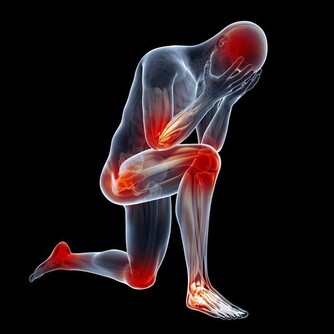

當人的年齡增大後,關節潤滑液會越來越少,潤滑度不夠,關節必定會出現磨損,這時候就會出現關節炎、骨刺、骨質疏鬆等疾病。

嚴重的甚至會導致骨關節壞死,這種屬於病理性關節響,一般伴隨著疼痛、活動受限,或者關節突然卡住。